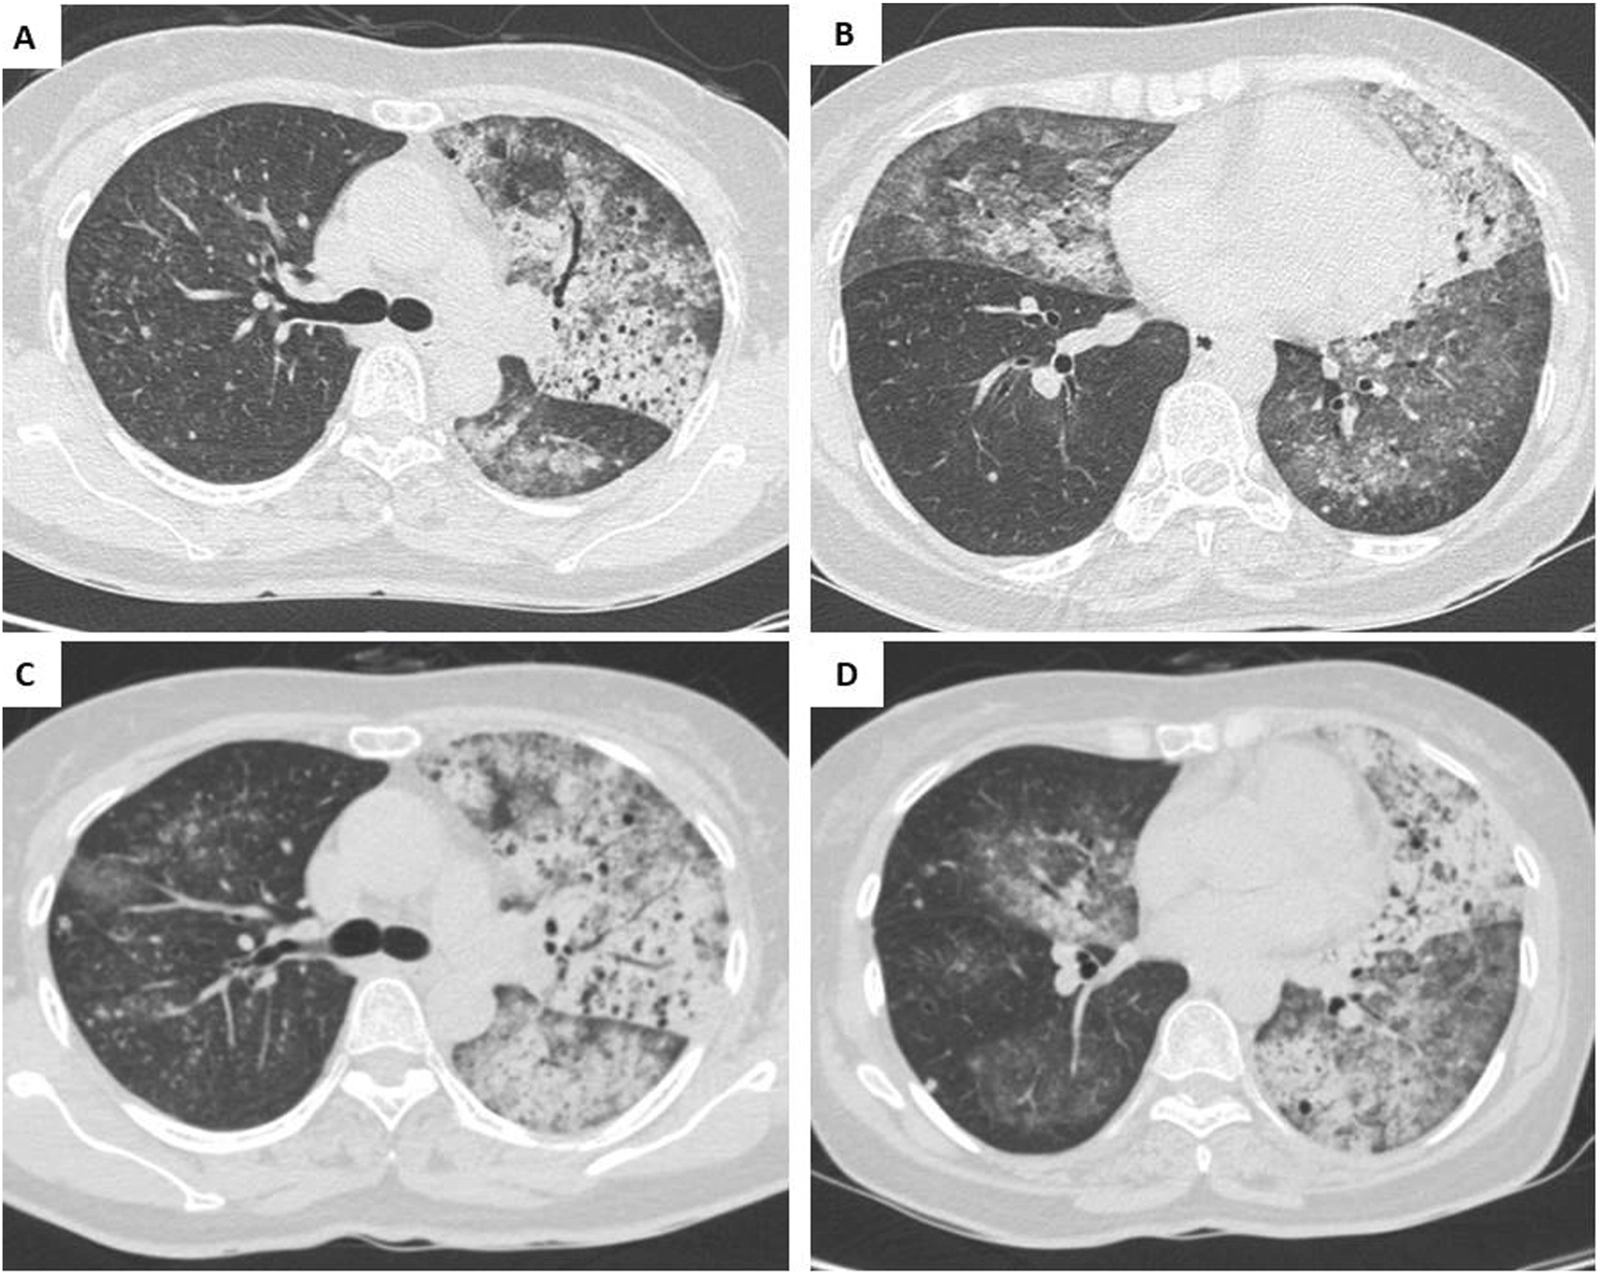

The patient started treatment with 80 mg of osimertinib daily from September 20th and had a significant clinical response. After just 3 days, her SpO2 level rose to 92%–95%, allowing for the discontinuation of CPAP. Oxygen therapy was subsequently tapered, and the patient was discharged after 10 weeks of hospitalization. In the following 2 months, the patient became fully independent of oxygen and had an performance status of 0–1 according to Eastern Cooperative Oncology Group (ECOG) [10]. The CT scan in November 2023 showed that the pulmonary lesions in both lungs had significantly decreased (shown in Figures 3A,B). After 6 months of treatment, the CT scan in March 2024 continued to show a reduction in lesions with no significant lesion in the right lung (shown in Figures 3C,D). Progression-free survival (PFS) on osimertinib reached 9 months by June 20, 2024. Following disease progression, a repeat biopsy of the primary lung lesion was performed. Molecular re-evaluation using the same NGS panel confirmed the persistence of the EGFR L858R mutation with a high VAF of 89.0%. No secondary resistance mutations, such as EGFR T790M or C797S, nor any bypass signaling alterations (e.g., MET amplification or KRAS mutations), were detected within the scope of the 15-gene analysis. Figure 4 details the clinical course, illustrating the temporal relationship between the diagnostic procedures, molecular profiling, and the patient’s subsequent response to therapy.

FIGURE 3